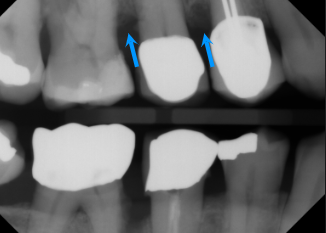

vertical bone loss

seen on radiographs as a non parallel line of bone loss

bone loss with furcation involvment

first sign of vertical bone loss

PDL space widens towards the crest

vertical bone loss M/D of #2

effects of bone loss on adjacent bone

inflammatory response to perio lesions and

more sclerotic/ radiolucent peripheral bone